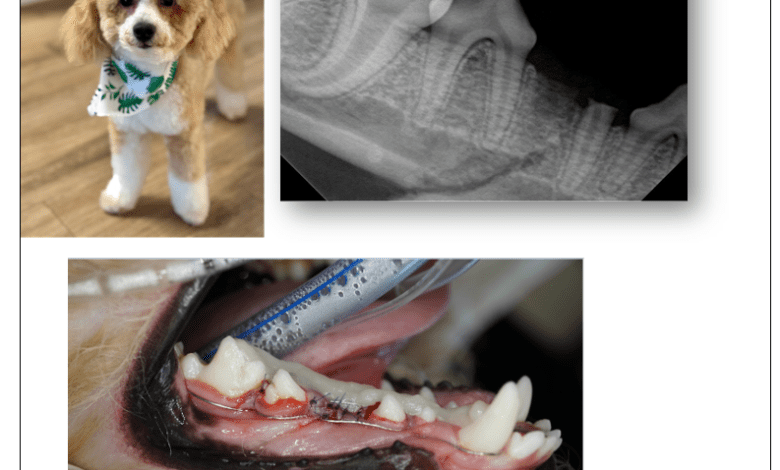

La investigación  se inició luego de que Palm Beach County Animal Care and Control (ACC por sus siglas en inglés) recibiera múltiples denuncias de empleados del centro, quienes señalaron que Hershman tenía un historial de agresiones físicas contra perros bajo su cuidado. Entre los reportes destacó un grave incidente ocurrido el 8 de mayo de 2025, que involucró a un cachorro de caniche miniatura llamado Cosmo.

De acuerdo con la investigación, Cosmo se encontraba en buen estado de salud inmediatamente antes de quedar a solas con Hershman. Poco después, miembros del personal escucharon un fuerte gemido y hallaron al cachorro sangrando por la boca, temblando y con dificultad para mantenerse en pie.

Exámenes veterinarios realizados en los días posteriores confirmaron que Cosmo presentaba una fractura de premolar y una fractura mandibular del lado derecho, lesiones que requirieron múltiples cirugías. Tanto el veterinario tratante como un especialista en odontología veterinaria concluyeron de manera independiente que las heridas fueron causadas por un impacto contundente de gran fuerza.

Los hallazgos de la investigación determinaron que el cachorro sufrió dolor severo e innecesario como resultado de las acciones de Hershman. Con base en estas conclusiones, las autoridades establecieron causa probable para imputarlo por crueldad animal agravada, conforme al estatuto FSS 828.12(2).